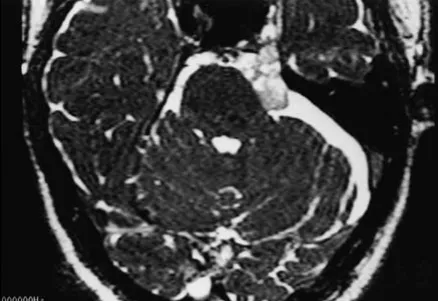

这是一个位于左侧桥小脑角(CPA)区和Meckel腔的表皮样囊肿。

轴位CISS图像显示稍低信号病灶延伸至Meckel腔。

轴位CISS图像显示内听道前方和Meckel腔内的稍低信号病灶(箭头指示)。

磁共振成像是检测表皮样囊肿的首选诊断方法。然而,蛛网膜囊肿和表皮样囊肿的鉴别有时仍然困难。在标准T1和T2加权自旋回波MR图像上,表皮样囊肿常难以与脑脊液区分;因此,已研究了其他成像序列。液体衰减反转恢复成像、弥散加权成像和CISS序列已被推荐用于表皮样囊肿的特征化。根据施罗德教授的经验,CISS是检测表皮样囊肿的最佳序列;CISS成像可以清晰区分脑脊液,并准确显示病变范围。在CISS图像上,表皮样囊肿通常表现为不均匀、低信号、边界不规则的结构。尽管大多数表皮样囊肿在T1加权图像上相对于脑脊液呈稍高信号,但CISS序列能更清晰地显示这些病变。